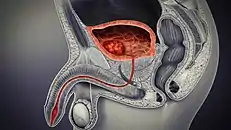

In humans, the bladder is a hollow muscular organ situated at the base of the pelvis. In gross anatomy, the bladder can be divided into a broad fundus (base), a body, an apex, and a neck.[3] The apex (also called the vertex) is directed forward toward the upper part of the pubic symphysis, and from there the median umbilical ligament continues upward on the back of the anterior abdominal wall to the umbilicus. The peritoneum is carried by it from the apex on to the abdominal wall to form the middle umbilical fold. The neck of the bladder is the area at the base of the trigone that surrounds the internal urethral orifice that leads to the urethra.[3] In males, the neck of the urinary bladder is next to the prostate gland.

In males, the prostate gland lies outside the opening for the urethra. The middle lobe of the prostate causes an elevation in the mucous membrane behind the internal urethral orifice called the uvula of urinary bladder. The uvula can enlarge when the prostate becomes enlarged.

The bladder is located below the peritoneal cavity near the pelvic floor and behind the pubic symphysis. In males, it lies in front of the rectum, separated by the recto-vesical pouch, and is supported by fibres of the levator ani and of the prostate gland. In females, it lies in front of the uterus, separated by the vesico-uterine pouch, and is supported by the elevator ani and the upper part of the vagina.[8]

The human bladder derives from the urogenital sinus, and it is initially continuous with the allantois. The upper and lower parts of the bladder develop separately and join around the middle part of development.[5] At this time the ureters move from the mesonephric ducts to the trigone.[5] In males, the base of the bladder lies between the rectum and the pubic symphysis. It is superior to the prostate, and separated from the rectum by the recto-vesical pouch. In females, the bladder sits inferior to the uterus and anterior to the vagina; thus its maximum capacity is lower than in males. It is separated from the uterus by the vesico-uterine pouch. In infants and young children the urinary bladder is in the abdomen even when empty.[16]